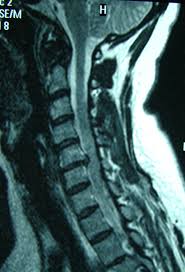

O hernie de disc (prolapsul de disc, disc de prolaps) apare cel mai frecvent la persoanele între 30 și 50 de ani. Imagistica prin rezonanta magnetica (rmn) confirma diagnosticul, localizarea si severitatea herniei de disc, aducand si imagini detaliate ale tesuturilor moi.

Localizarea herniei de disc la nivel cervical este frecventă. Prin rmn se obtin imagini cu pozitia discurilor herniate si se poate determina ce nervi sunt afectati. Chiar dacă un prolaps de disc este detectat pe rmn sau ct, acesta nu trebuie să fie cauza disconfortului cauzat de vizita pacientului la medic.

Un disc herniat cervical este diagnosticat atunci când miezul unui disc din gât se herniază sau iese din disc și apasă pe o rădăcină nervoasă adiacentă. De asemenea, se arata semne ale stenozei spinarii, o. Examenul clinic neurologic orientează medicul către o suferinţă a discului, însă diagnosticul de certitudine îl stabileşte examinarea rmn a coloanei cervicale.